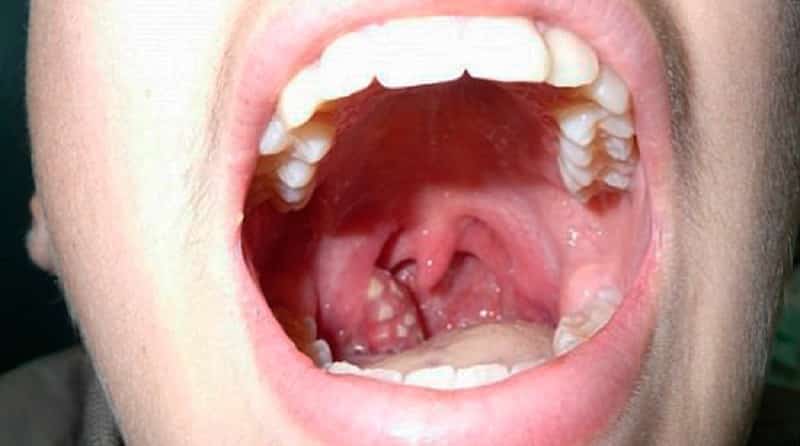

Если у ребенка появился белый налет на гландах (фото), как можно лечить это состояние в домашних условиях, если нет возможности сразу обратиться к врачу?

Белый налет и воспаление на гландах

Прежде всего, важно предотвратить дальнейшее распространение инфекции. Для этого необходимо обработать слизистые оболочки миндалин и гортани раствором щелочи, который эффективно подавляет патогенные микроорганизмы, замедляя их рост и развитие. Наиболее известным и доступным щелочным средством является обычная пищевая сода.